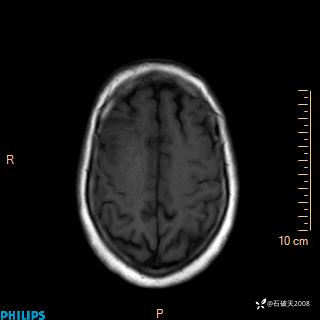

2020.11.14MR

FLAIR